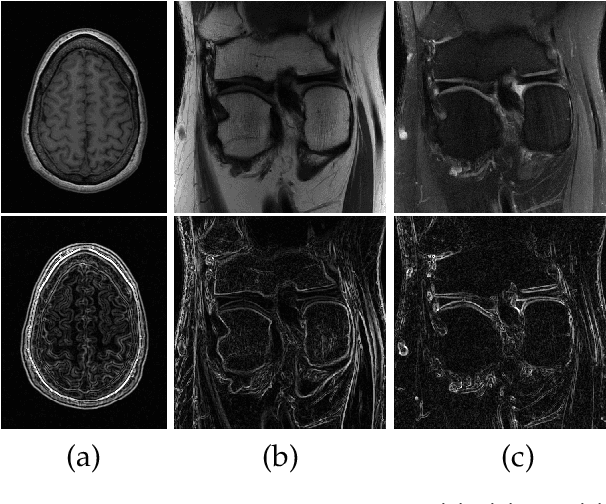

Abstract:Fast and accurate MRI reconstruction is a key concern in modern clinical practice. Recently, numerous Deep-Learning methods have been proposed for MRI reconstruction, however, they usually fail to reconstruct sharp details from the subsampled k-space data. To solve this problem, we propose a lightweight and accurate Edge Attention MRI Reconstruction Network (EAMRI) to reconstruct images with edge guidance. Specifically, we design an efficient Edge Prediction Network to directly predict accurate edges from the blurred image. Meanwhile, we propose a novel Edge Attention Module (EAM) to guide the image reconstruction utilizing the extracted edge priors, as inspired by the popular self-attention mechanism. EAM first projects the input image and edges into Q_image, K_edge, and V_image, respectively. Then EAM pairs the Q_image with K_edge along the channel dimension, such that 1) it can search globally for the high-frequency image features that are activated by the edge priors; 2) the overall computation burdens are largely reduced compared with the traditional spatial-wise attention. With the help of EAM, the predicted edge priors can effectively guide the model to reconstruct high-quality MR images with accurate edges. Extensive experiments show that our proposed EAMRI outperforms other methods with fewer parameters and can recover more accurate edges.